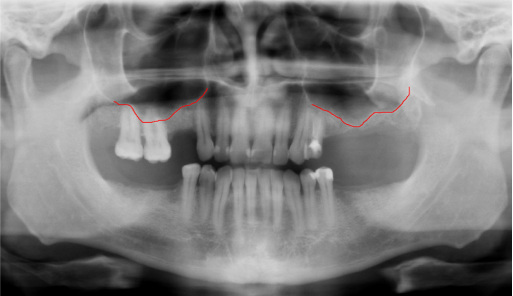

After